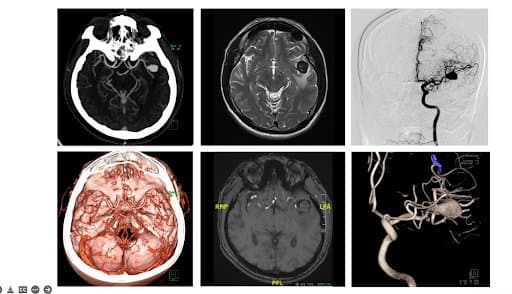

Rechts werden unterschiedliche Seiten derselben Realität, nämlich einer dreidimensionalen Pathologie, durch verschiedene Methoden dargestellt. Sobald das 3D-gedruckte Modell fertig ist, sind jedoch all diese verschiedenen Informationen in einem Stück vereint. Links ist ein laufender operativer Eingriff zu sehen.

Patientenperspektive: Ein 55-jähriger Patient mit verdächtigen Krampfanfällen wurde untersucht, indem zunächst mittels CT- und MRT-Scans eine Aufnahme des Gehirns erstellt wurde. Die Hirnscans zeigten eine 1,5 cm große Masse in der Sylvischen Fissur zwischen dem Frontal- und Temporallappen des Gehirns. Die erste Annahme war, dass es sich um einen riesigen Tumor oder möglicherweise ein Aneurysma handelte. Weitere Scans bestätigten, dass in diesem Fall ein großes Aneurysma (über 2 cm) mit Thrombose vorlag. Tritt in einem Aneurysma ein Thrombus auf, können kleine, dicke Blutgerinnsel in die distalen Arterien wandern und diese blockieren. Diese Blockaden stoppen die Blutversorgung wichtiger Bereiche des Gehirns, was zu einem Schlaganfall führt.

Die Option eines chirurgischen Eingriffs wurde vorgeschlagen, nachdem das Ärzteteam bereits die digitalen Modelle fortschrittlicher Bildgebungstechnologien wie CT, MR, MR-Angiographie und digitale Subtraktionsangiographie mit 3D-Rotation ausgewertet hatte, auf deren Grundlage die Operationsplanung mit dem Patienten besprochen wurde. In akuten Fällen wie diesem, wo eine OP dringend erforderlich ist, kann ein 3D-Modell bei der Verbildlichung und Einübung eines Eingriffs helfen und zudem zu einem besseren Verständnis des Eingriffs seitens der Behandelten beitragen.

Wie in der digitalen Simulation zu sehen ist, lassen sich Farbe, Winkel und Position der digitalen Modelle anpassen und die letztendliche Operation kann simuliert werden. Die Abbildung zeigt das komplexe Verhältnis der zentralen Prismen mit den darunterliegenden Blutgefäßen. Das Modell liefert Operationsteams die Möglichkeit, bereits vor der OP die Beziehung der wichtigsten Verzweigungen unter dem Gehirn und das simulierte Clipping anzusehen. Indem schon bei der OP-Vorbereitung visuelle Informationen zur Verfügung stehen, wird die Effizienz von Eingriffen gesteigert.